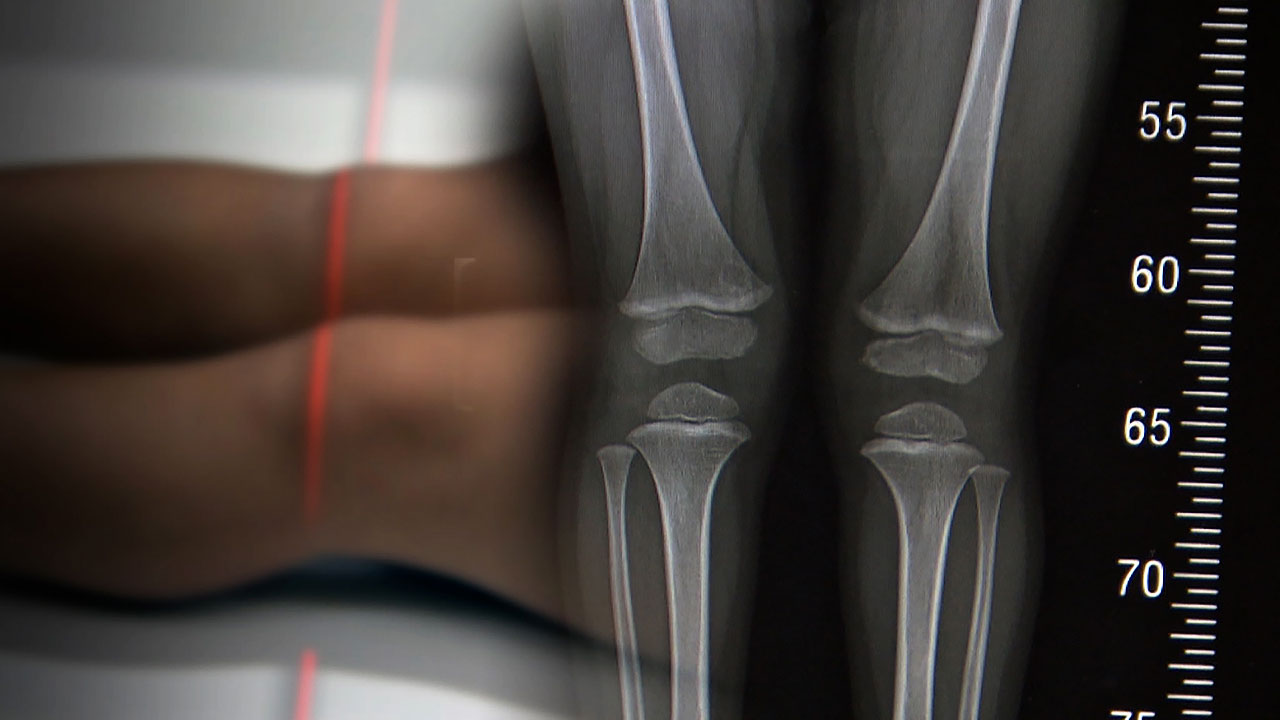

성장판

아빠 키와 엄마 키를 더해서 하는 거는 정말 추정치인 거고, 만약에 그게 맞다면 사실은 형제자매가 다 키가 똑같아야 되는데 그렇지 않잖아요. 이거는 사실은 경향을 보는 것뿐이고, 성장판을 찍는 거는 요새 높게 보고하는 데는 95%까지 보고합니다. 꽤 정확해요.